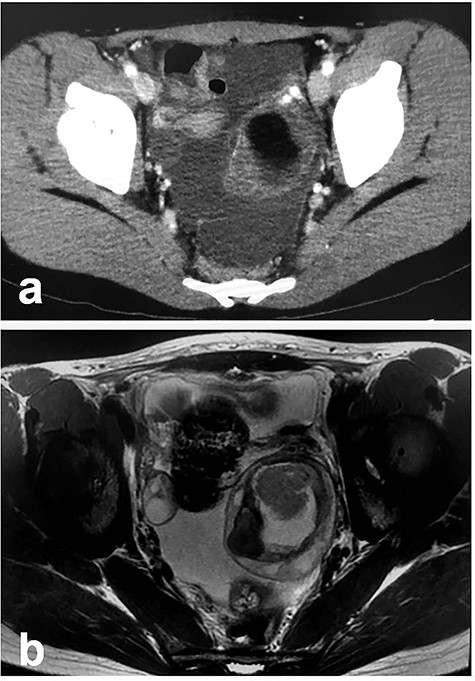

Patient 2: In a 14-year-old girl with abdominal pain, enhanced CT showed a left ovarian tumor (Fig. 3a). Further examination, including MRI, revealed an ovarian MCT (70 cm × 67 cm; Fig. 3b). She underwent laparoscopic surgery, during which the tumor was placed in a specimen retrieval bag. The contents were aspirated using a newly developed soft-cup aspirator set (Hakko Co., Tokyo, Japan) [9], and the tumor was excised without content spillage (Fig. 4). The excised margins were continuously oversewn using the V-Loc™ absorbable wound closure device (Covidien Healthcare, Minneapolis, MN). Pathologic examination confirmed the diagnosis of MCT. She has been doing well without evidence of recurrence. She subsequently established a regular menstrual cycle.